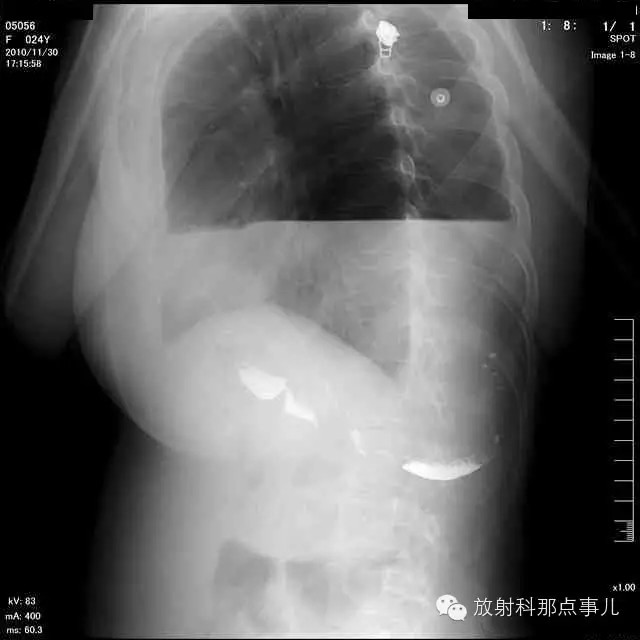

24岁,女性,腹痛渐加重并呕吐。

患者系顺产后18天产妇,产后感觉腹部疼痛不适,自认为正常反应,近两日因胸闷、腹部疼痛加剧伴呕吐来院就诊。

门诊腹部透视发现左侧胸腔巨大气液平面,为排除膈疝口服钡剂,但造影剂未见进入胃内。嘱住院,外科给予胃肠减压、补液等处理常规处理(未引流出明显气、液体)。5个半小时后再次检查,见少量造影剂进入消化道;为进一步了解情况,予泛影葡胺分别经胃管推注及口服,但均未进入胃内。当天进行外科急诊手术。

大部分胃、脾及横结肠均经过胸肋三角疝入左侧胸腔内,并见疝环形成。